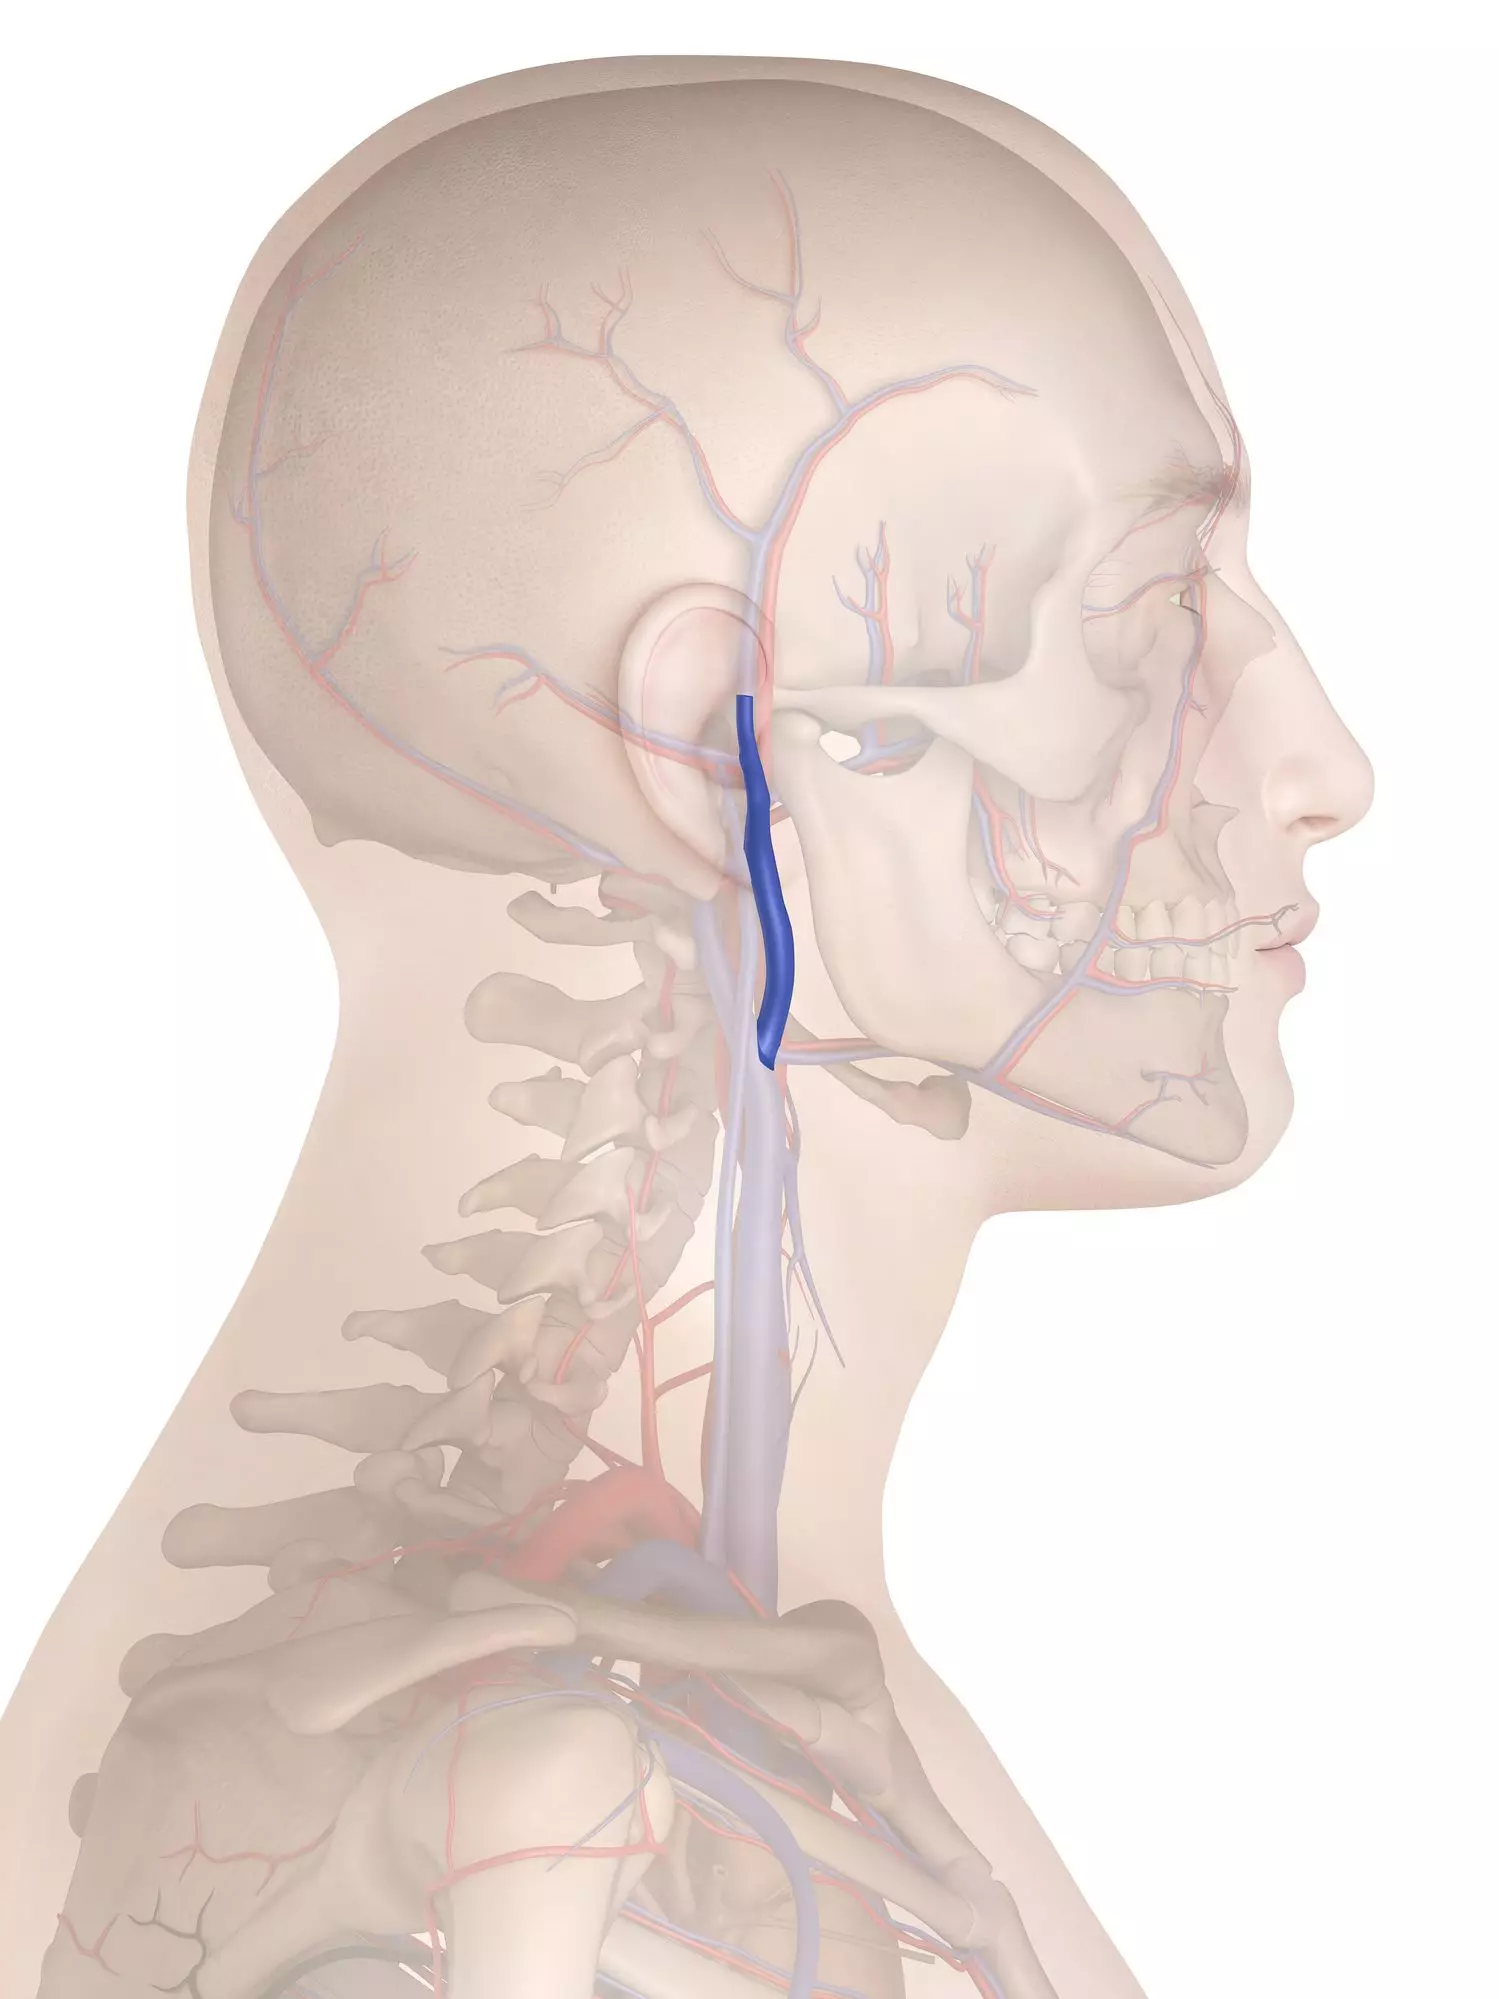

Анатомия внутренней яремной вены: КТ изображения